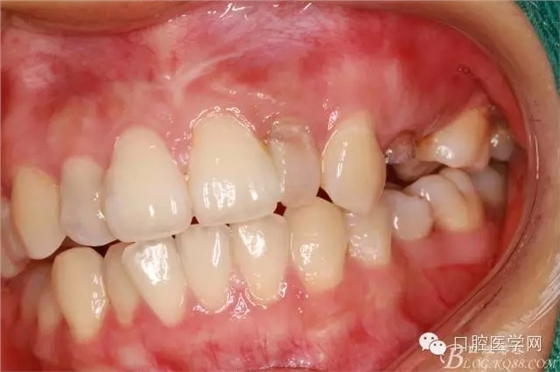

術(shù)前口內(nèi)照